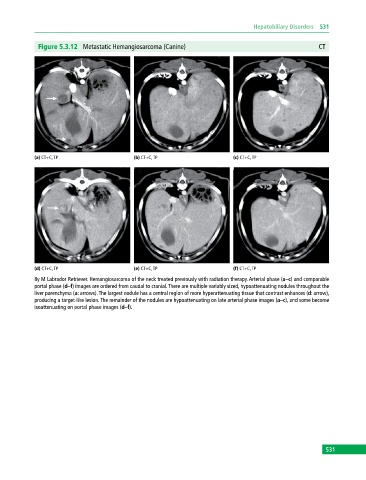

Figure 5.3.12 Metastatic Hemangiosarcoma (Canine) CT

(a) CT+C, TP (b) CT+C, TP (c) CT+C, TP

(d) CT+C, TP (e) CT+C, TP (f) CT+C, TP

8y M Labrador Retriever. Hemangiosarcoma of the neck treated previously with radiation therapy. Arterial phase (a–c) and comparable

portal phase (d–f) images are ordered from caudal to cranial. There are multiple variably sized, hypoattenuating nodules throughout the

liver parenchyma (a: arrows). The largest nodule has a central region of more hyperattenuating tissue that contrast enhances (d: arrow),

producing a target‐like lesion. The remainder of the nodules are hypoattenuating on late arterial phase images (a–c), and some become

isoattenuating on portal phase images (d–f).